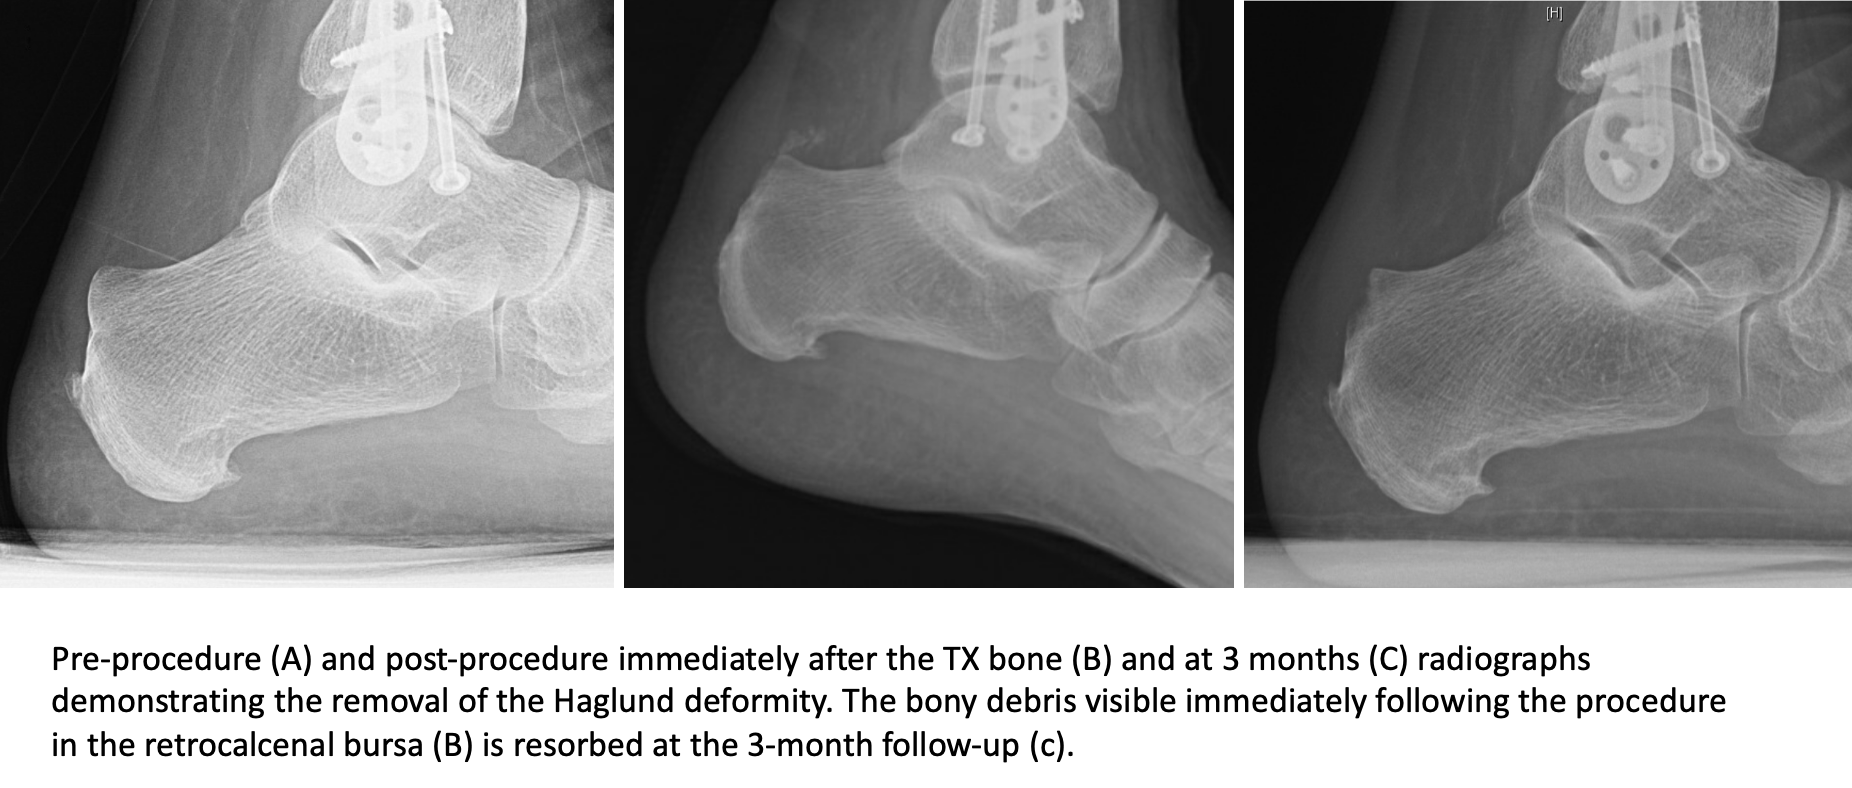

Interesting radiology cases from daily practice and a personal reference. This deformity leads to retrocalcaneal bursitis. It refers to the mechanical irritation between the posterior section of the calcaneus (heel bone) and the achilles tendon. The authors describe a new method of radiologic measurement of haglund's deformity, based on a radiologic study of 31 feet operated for posterior heel pain and more especially for calcaneal tendinopathies related to deformity of the calcaneus, and on a series of 60 asymptomatic feet. Operative management of haglund's deformity in the non athlete:

The authors describe a new method of radiologic measurement of haglund's deformity, based on a radiologic study of 31 feet operated for posterior heel pain and more especially for calcaneal tendinopathies related to deformity of the calcaneus, and on a series of 60 asymptomatic feet. As associated problems such as heel bursitis settle, the size of the lump should reduce, but the bony why is it called haglunds deformity? Radiographic evaluation of haglund's deformity. Haglund deformity is most common in young women who wear high heeled shoes or pumps. This deformity leads to retrocalcaneal bursitis. Haglund's deformity is named after patrick haglund, who defined the condition in 1927. Haglund's deformity can cause the development of bursitis, which is a painful condition in the heel. Haglund's syndrome is a group of signs and symptoms consisting of haglund's deformity (which is an exostosis of the posterior calcaneal tuberosity) in combination with retrocalcaneal bursitis.

Correct shoes that are supportive may prevent it. As associated problems such as heel bursitis settle, the size of the lump should reduce, but the bony why is it called haglunds deformity? Radiographic evaluation of haglund's deformity. The authors describe a new method of radiologic measurement of haglund's deformity, based on a radiologic study of 31 feet operated for posterior heel pain and more especially for calcaneal tendinopathies related to deformity of the calcaneus, and on a series of 60 asymptomatic feet. This deformity leads to retrocalcaneal bursitis. Haglund deformity, also known as a pump bump, bauer bump, or mulholland deformity, is defined as bony enlargement formed at the posterosuperior aspect of the calcaneum. Haglund's deformity is a bony enlargement at the level of the posterior part of the heel. The primary symptom of haglund's deformity is pain at the back of the heel. Haglund's deformity is named after patrick haglund, who defined the condition in 1927. There is a noticeable swelling on the back of heel also called bump. This includes home remedies and. Haglund's deformity is a bony enlargement on the back of the heel. Haglund's syndrome is a group of signs and symptoms consisting of haglund's deformity (which is an exostosis of the posterior calcaneal tuberosity) in combination with retrocalcaneal bursitis.

Radiographic evaluation of haglund's deformity.

Haglund deformity, also known as a pump bump , bauer bump, or mulholland deformity, is defined as bony enlargement formed at the posterosuperior aspect of the calcaneum. You may see reddening and swellings at the heel, which may be very. However, often patients will present with a combination of achilles tendinopathy, retrocalcaneal bursitis or retrocalcaneal exostosis in addition to a haglund's deformity. The authors describe a new method of radiologic measurement of haglund's deformity, based on a radiologic study of 31 feet operated for posterior heel pain and more especially for calcaneal tendinopathies related to deformity of the calcaneus, and on a series of 60 asymptomatic feet. Haglund deformity, also known as a pump bump, bauer bump, or mulholland deformity, is defined as bony enlargement formed at the posterosuperior aspect of the calcaneum. Haglund's deformity also goes by the name of haglund's disease and pump bump. It affects the bone and the soft tissues. Haglund's deformity is an abnormal bump in the heel bone. Halgund's deformity is a condition in which a bony enlargement is formed in the heel. Operative management of haglund's deformity in the non athlete: Haglund's deformity is a bony enlargement at the level of the posterior part of the heel. Correct shoes that are supportive may prevent it. An example is haglund's deformity, a condition caused by a bump on the back of the heel.

Radiographic evaluation of haglund's deformity. The soft tissue near the achilles tendon becomes irritated when the bony enlargement rubs against shoes. Pump bump is named after patrick haglund, a swedish orthopedic surgeon, who first described the condition back in 1927. 1 an isolated haglund's deformity can lead to posterior heel pain in runners due to adjacent soft tissue impingement by the heel counter. Related online courses on physioplus. When this bony enlargement rubs against the achilles tendon and overlying bursa, inflammation of the retrocalcaneal bursa occurs. Haglund's deformity is where bone grows on the heel bone (calcaneus). Haglund's deformity is named after patrick haglund, who defined the condition in 1927. Haglund's deformity can cause the development of bursitis, which is a painful condition in the heel. However, often patients will present with a combination of achilles tendinopathy, retrocalcaneal bursitis or retrocalcaneal exostosis in addition to a haglund's deformity. Posterosuperior calcaneal exostosis) terminology haglund syndrome is a painful the haglund syndrome: As associated problems such as heel bursitis settle, the size of the lump should reduce, but the bony why is it called haglunds deformity? Haglund's deformity was described for the first time in 1928.